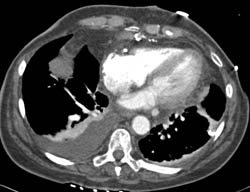

Aortic Dissection